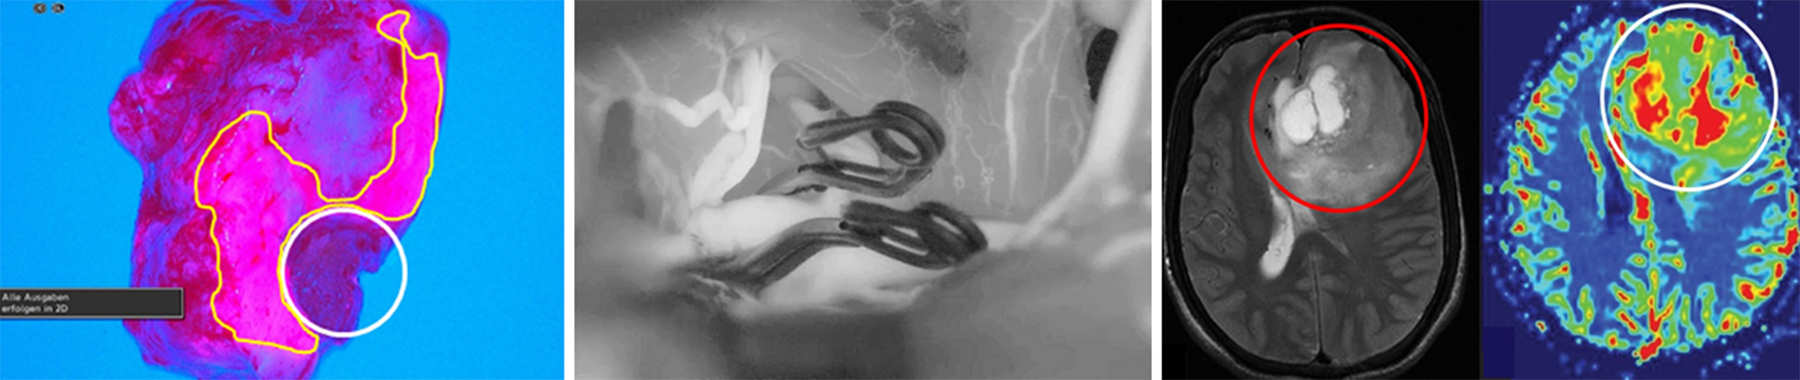

Tumore und Gefäßneubildungen des Gehirns und Rückenmarks sind unser Spezialgebiet. Zusammen mit der Neuroradiologie, Neurologie und der Neuro-Intensivmedizin bieten wir das gesamte Spektrum in der Diagnostik und der Ersttherapie von Schlaganfällen und Hirnblutungen auf universitärem Niveau.

Für die Nachbehandlungen von Tumorerkrankungen stehen uns die Partner aus der Strahlentherapie wie auch der Onkologie zur Verfügung. Hirntumoren und Hirnmetastasen werden auf höchstem Niveau versorgt. Hierzu arbeiten wir mit den Fachgebieten der DIAKO und der Malteser eng zusammen und sind auch mit den universitären Tumorzentren (CCC) in Kiel und Hamburg vernetzt.

Im Operationssaal bedarf die Behandlung von Tumoren und Gefäßveränderungen im Hirnstamm und Rückenmark eines besonderen Vorgehens. Minimalinvasive, mikrochirurgische und extrem hochauflösende Optiken mit Unterstützung eines elektrophysiologischen Monitorings sind gefordert.

Neu in der DIAKO ist das ORBEYE, welches das Operationsmikroskop ersetzt und nun ein 26-fache digitale Bildvergrößerung in 3D möglich macht. Ergänzend nutzen wir im OP eine Neuronavigation für den präzisen Zugang, den intraoperativen Ultraschall sowie endoskopische Techniken und eine spezielle Neuroanästhesie. Damit ist uns eine weitere Verbesserung der klinischen Ergebnisse mit Erhalt aller neurologischen Funktionen möglich.

Es ist weltweit der erste Bericht von einer erfolgreichen Operation am Hirnstamm mit dem 3D-4K Exoskop „Orbeye”.

Ein Cavernom ist eine Blutgefäßveränderung, welches bei dieser Patientin in der ganz zentralen Region des Gehirns, dem Hirnstamm, gelegen war. Kopfschmerzen, Doppelbilder und Gefühlsstörungen in Armen und Beinen waren die Beschwerden, mit denen sich die Patientin bei Prof. Dr. Jan Regelsberger in der DIAKO vorstellte.